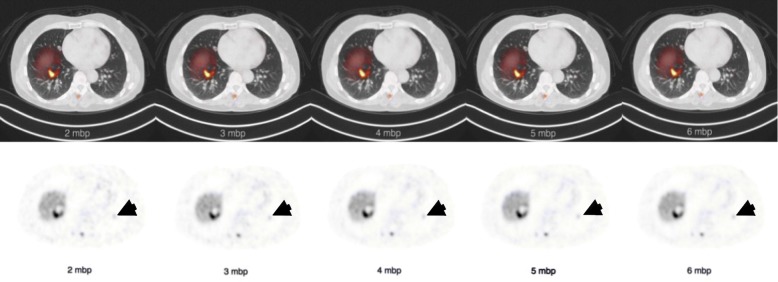

The results of the lesion detectability assessment are summarized in Table 5. It can be appreciated that the 2 mbp has a significant lower lesion detectability rate than the other reconstructions compared with the 6 mbp. In Fig. 4, a lesion located in the lower part of the left lung is shown for a single patient. A Friedman test (χ2 (4) = 122.54, p < 0.001) with an additional Dunn-Bonferroni post hoc test confirmed that only the 2 mbp had a significant difference (p = 0.007) in lesion categories with the 6 mbp reference reconstructions. Furthermore, the table shows that the interobserver agreement was almost perfect for 2 mbp (Fleiss 휅 = 0.81) and substantial (Fleiss 휅 = 0.79-0.74) for the other reconstructions.

Fig. 4.

Example of transversal PET/CT fusion and PET only images. The images show multiple lesions including one lesion in the liver and one lesion with low uptake in the left basal lung (arrow). The lung lesion was detected on 3-6 mbp and was missed on 2 mbp. All other lesions were detected on all mbps